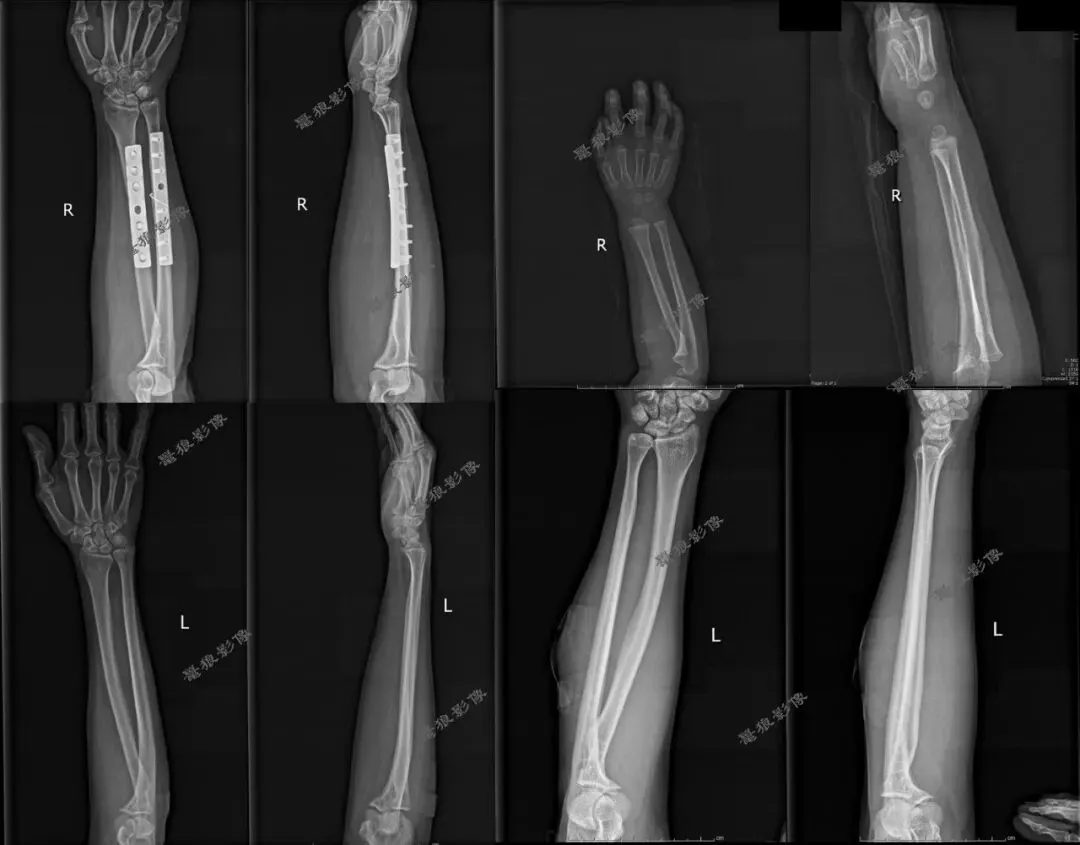

七、需要警惕以下情况发生

一、难道桡尺骨正侧位就必须全部伸直肘部或者全部弯曲肘部90°拍摄?说到底还是因为这样拍摄是标准的,有利于诊断。

三、假如说病人是靠近腕关节那一侧的桡尺骨有问题时,我们拍摄桡尺骨正侧位也只包括一侧腕关节时,这样的拍摄方法(全部伸直或者全部弯曲)也许不会发现此问题。但是病人是肘关节那一侧的桡尺骨有问题时,我们拍摄桡尺骨必须要包括肘关节时,这样的拍摄方法(全部伸直或者全部弯曲)就有问题啦!桡尺骨侧位片伸直显示不出肘关节侧位,桡尺骨正位片弯曲90°显示不出肘关节正位,我们都没法查看肘关节的解剖细节!